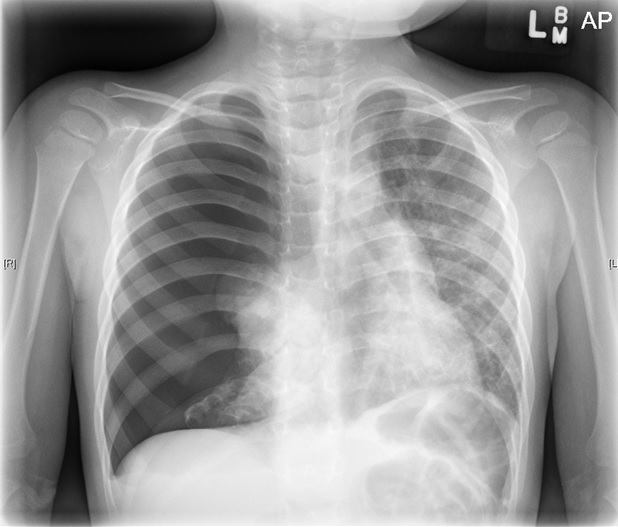

At presentation in the ED, the patient’s vital signs were normal. Physical examination findings were unremarkable except for absent right-sided breath sounds and abdominal retractions. Chest radiographs showed a spontaneous right tension pneumothorax (Figure 1). A chest tube was placed, and a computed tomography (CT) scan of the chest was ordered (Figure 2), the latter of which showed bilateral diffuse cystic lesions leading to honeycombing. The patient was admitted for further workup.

Figure 1. Chest radiograph showed a spontaneous right tension pneumothorax.

Discussion. Spontaneous pneumothorax (SP) is rare and may have nonspecific presentations in children. SP is defined as a rupture of visceral pleura with air accumulation within the pleural space, which can be primary or secondary. Tension pneumothorax (TP) creates increased intrathoracic pressure, leading to mediastinal shift, respiratory distress, hypoxia, and hemodynamic instability, as illustrated in Figure 1.1